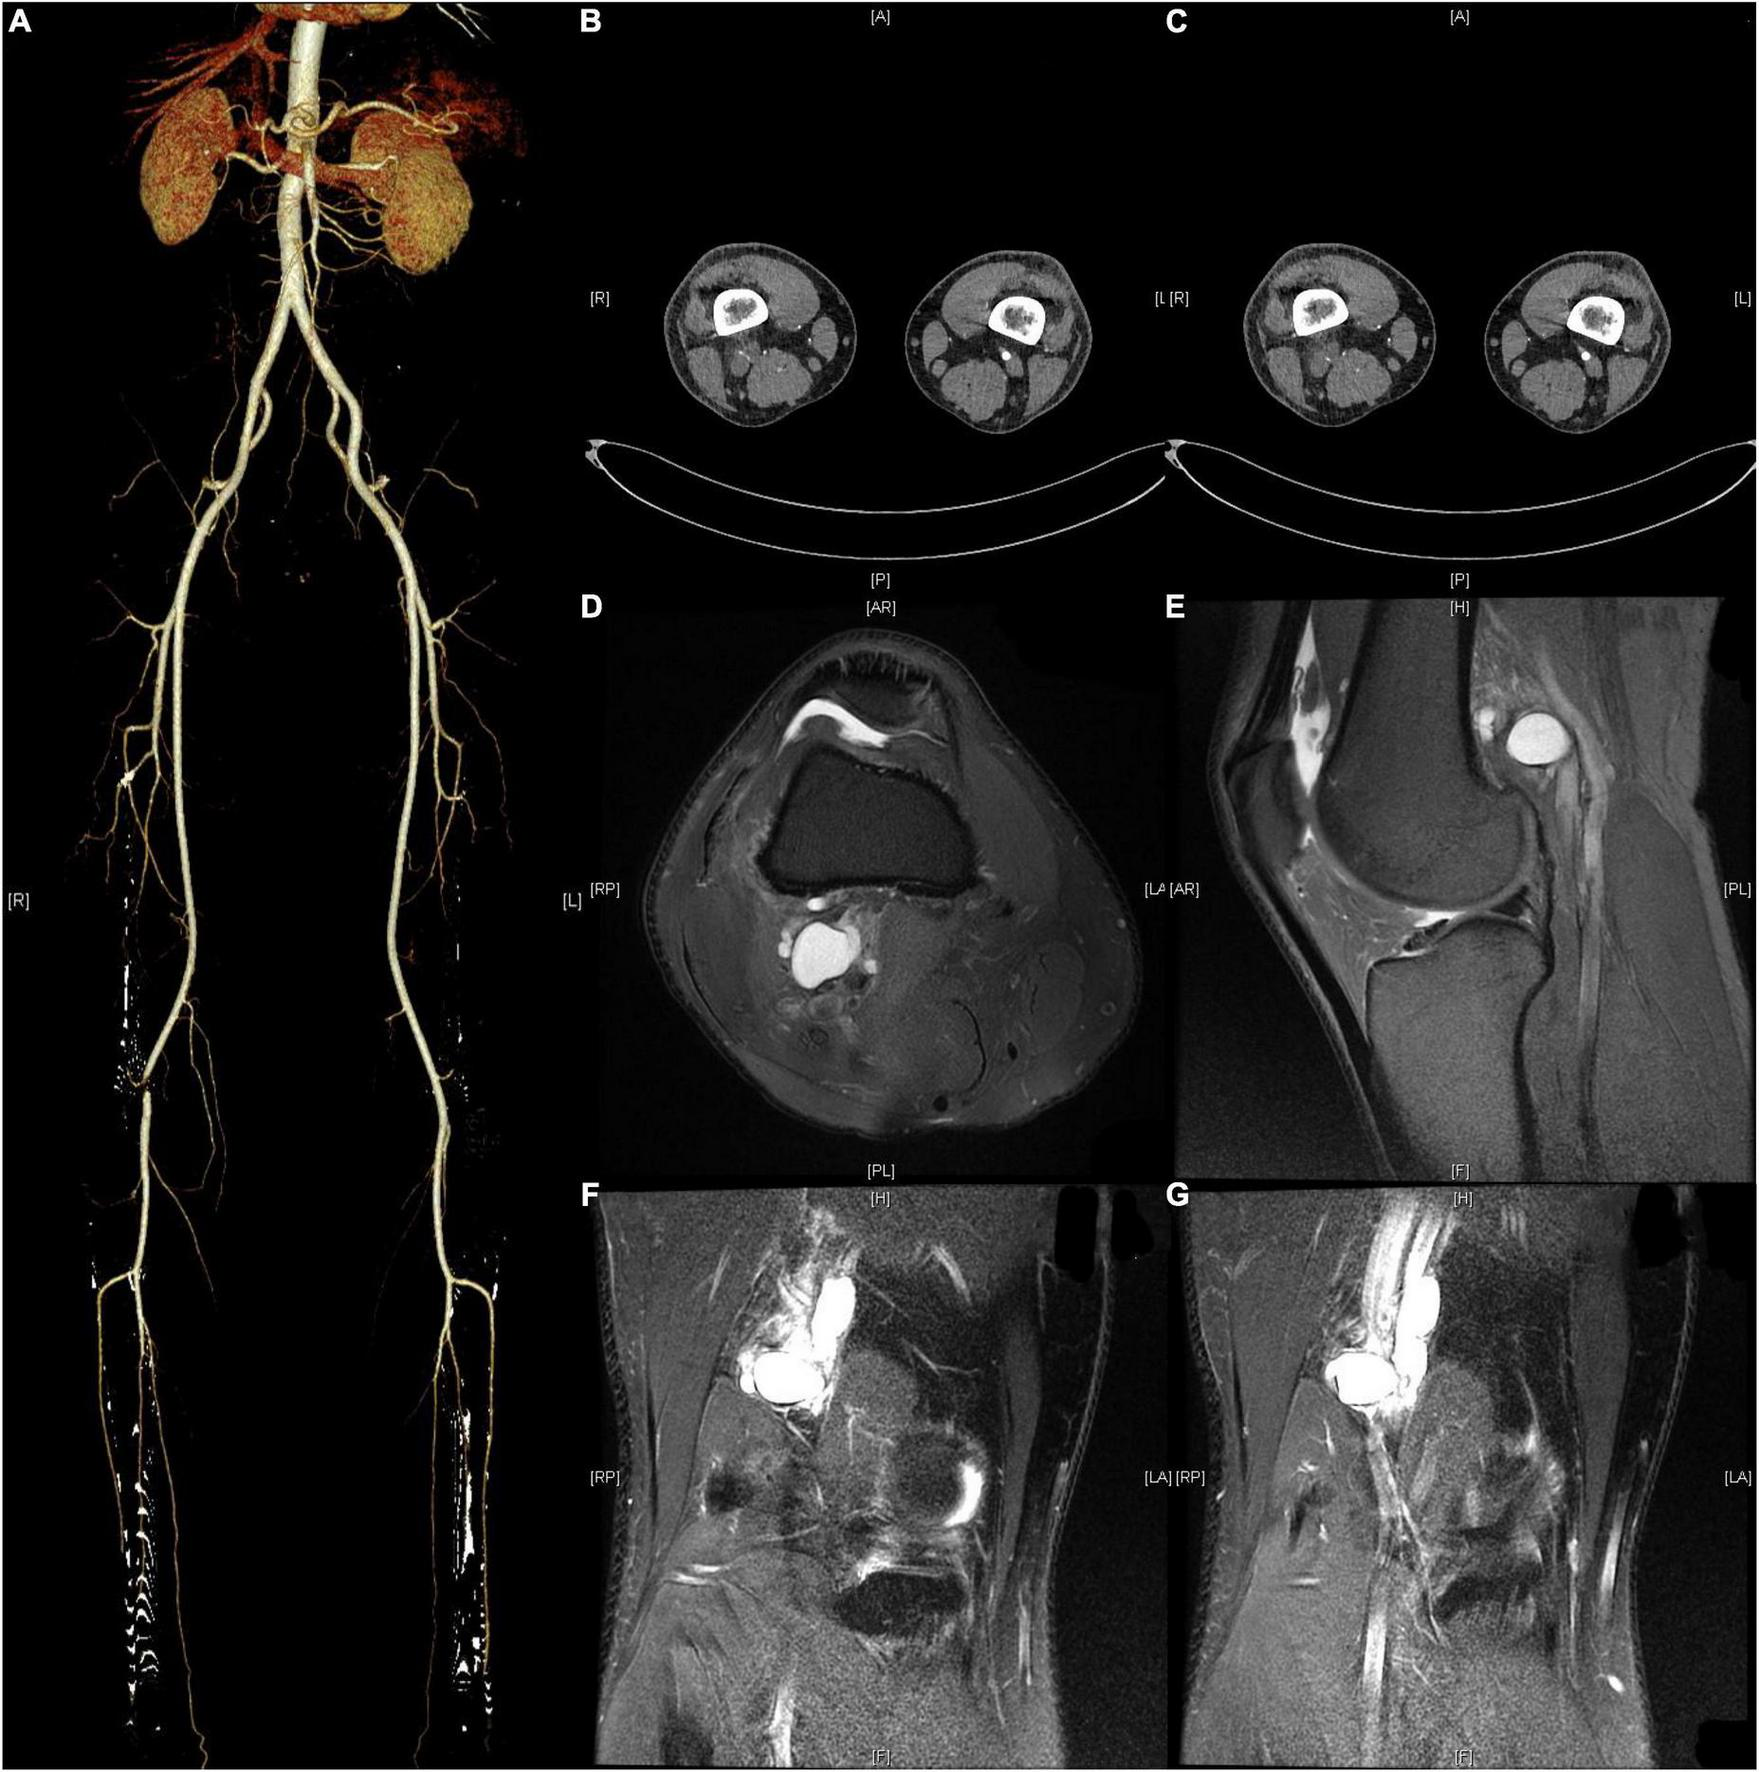

Ultrasound showed reduced flow velocity in the right lower limb artery, superficial femoral artery (34 cm/s), popliteal artery (24 cm/s), anterior tibial artery (20 cm/s), posterior tibial artery (17 cm/s), and peroneal artery (24 cm/s), with absent triphasic waves (Figure 1). CTA suggests severe stenosis and almost complete occlusion of the P1 segment of the popliteal artery (Figures 2A–C). MRI suggested that the popliteal artery was compressed by an oval cyst with high signal intensity on T2-weighted, which is 1.7*2.5*3.1 cm in volume (Figures 2D–G). A diagnosis of popliteal artery entrapment syndrome is proposed.

FIGURE 2

Preoperative CTA and MRI. (A–C) CTA showed severe stenosis of the popliteal artery in the right lower extremity. (D–G) MRI suggested that the popliteal artery was compressed by an oval cyst with high signal intensity on T2-weighted, which is 1.7*2.5*3.1 cm in volume.